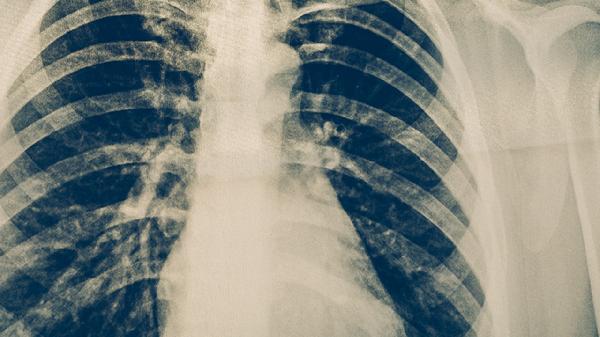

肺結核患者可通過呼吸道隔離、環(huán)境消毒、個人防護、接觸者篩查、規(guī)范治療等方式實現(xiàn)有效隔離。肺結核是由結核分枝桿菌引起的慢性傳染病,主要通過飛沫傳播。

對共同居住者、同事等密切接觸者進行結核菌素試驗和胸部X線篩查。15歲以下兒童及免疫缺陷者需預防性服用異煙肼片3-6個月。發(fā)現(xiàn)疑似病例立即轉診至定點醫(yī)院,建立接觸者健康檔案跟蹤監(jiān)測2年。